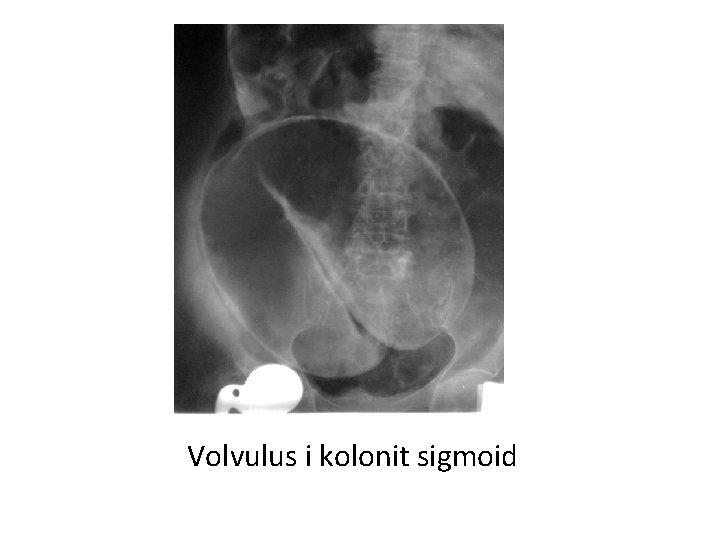

Volvulus i kolonit sigmoid